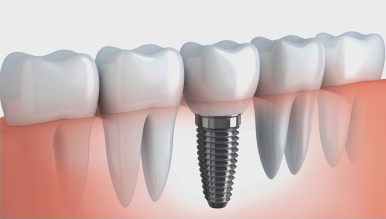

瑞士ITI/瑞士Nobel即刻种植技術